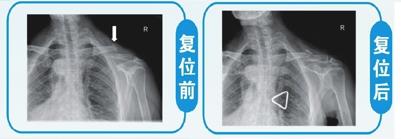

(3)锁骨骨折 此类骨折复位及固定困难但生长快,不必强求解剖复位,愈合合对肩关节功能没有影响。